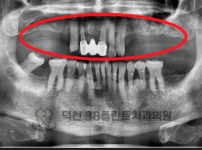

치료전후